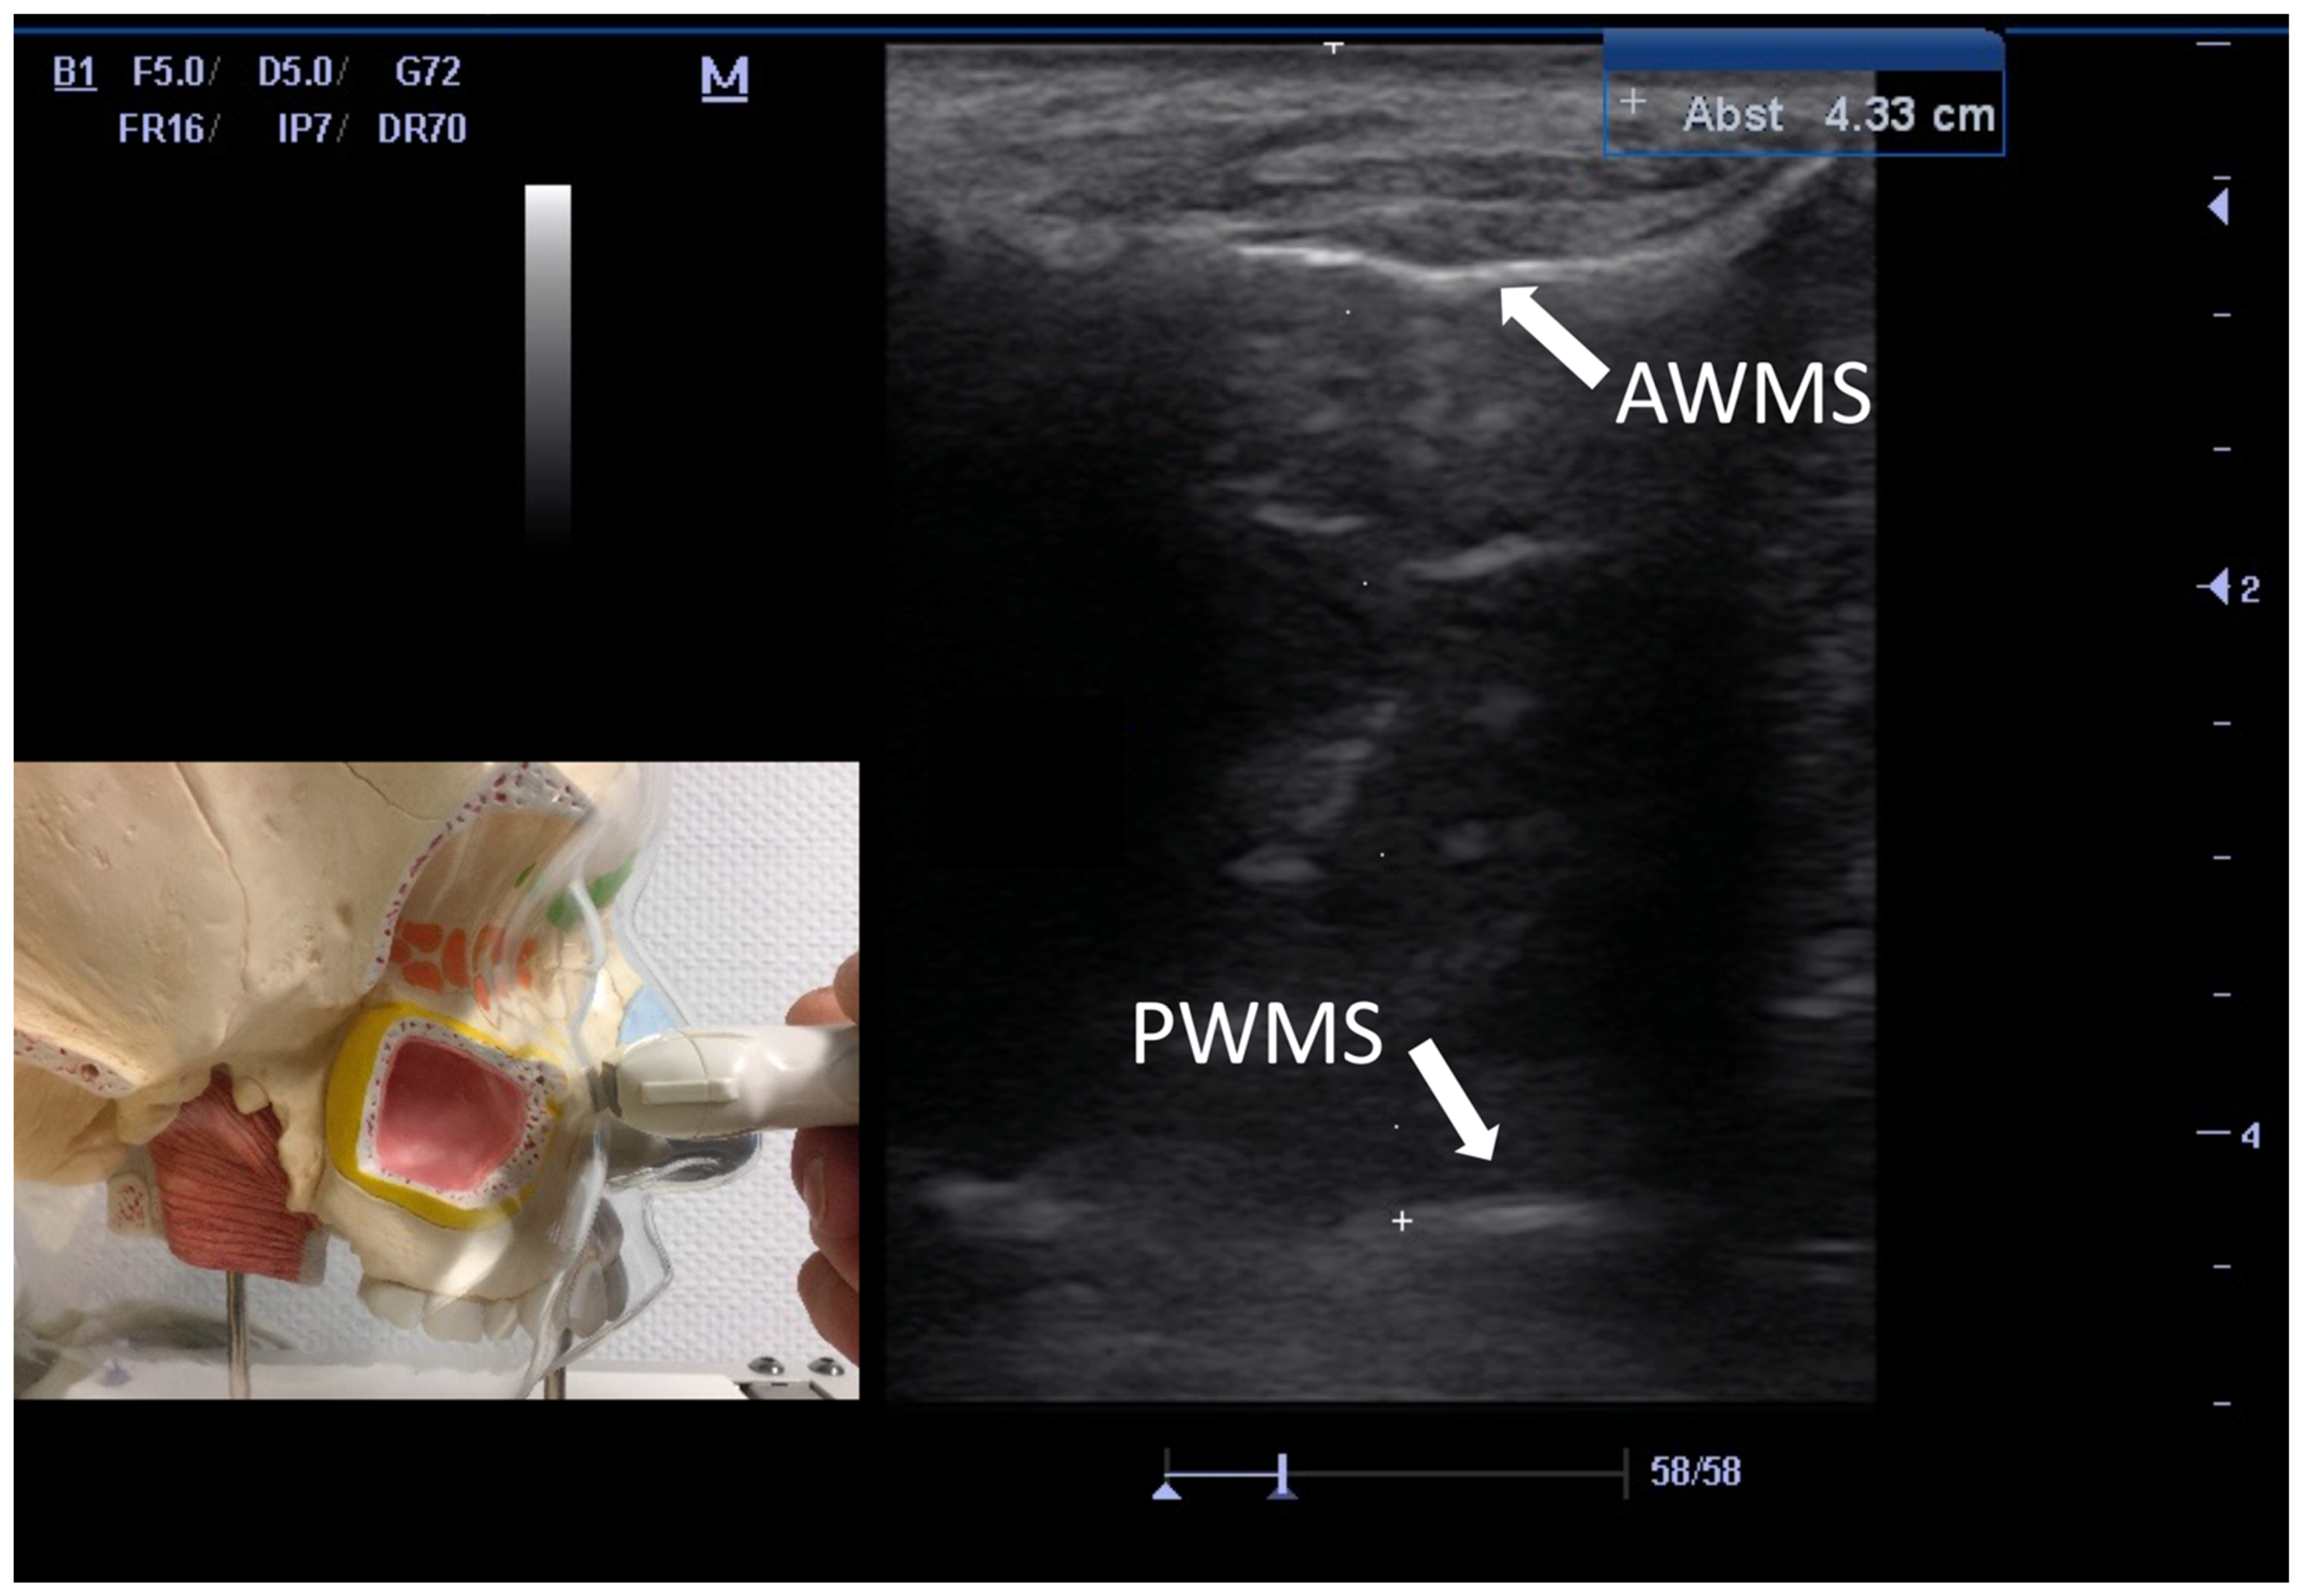

2.5.2. Evaluation of B-Mode US